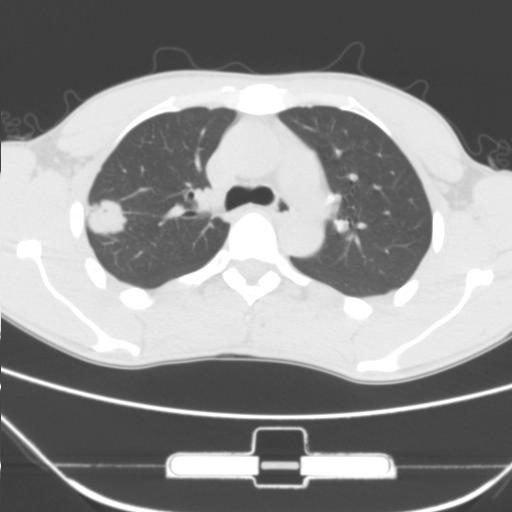

右肺上叶后段近胸膜下结节样异常密度灶,似见分页及毛刺,考虑右肺上叶周围型肺ca,建议穿刺病理检查

缺乏病史,症状体征,但这个孤立结节具备了几乎所有的恶性征象:分叶,毛刺,空泡征,胸膜凹陷征,血管集束。

考虑右肺上叶后段周围型肺癌。